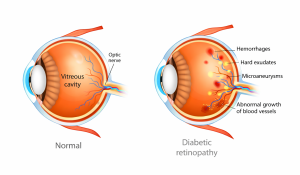

This is a more advanced stage of the disease. When blood supply to the retina is reduced, the eye responds by growing new abnormal blood vessels. These vessels are fragile and bleed more easily, increasing the risk of more severe vision problems such as vitreous haemorrhage, membranes and traction on the retina, retinal detachment, or even high eye pressures.

- Surgical Treatment

In advanced cases, surgery is necessary when bleeding or scar tissue affect the retina or threaten vision. Surgical management of diabetic retinopathy requires careful judgement, precise technique, and experience in handling complex retinal conditions. Advanced cases often involve bleeding, scar tissue, or traction on the retina, which may coexist with other eye problems such as cataract or glaucoma. Management in these situations benefits from a retinal specialist with experience in both medical and surgical treatment planning, so that timing, approach, and follow-up care are appropriately coordinated. - Individualised Long-Term Care

While advanced diabetic eye disease can be severe, it does not mean that no treatment is possible. An eye with proliferative diabetic retinopathy is eminently treatable, and it is important to recognise that appropriate and timely management decisions on medical and surgical treatment need to be made by an experienced retinal specialist, in order to achieve the best possible outcomes.

Effective treatment will stop progression of the disease to even more severe stages and prevent complications, such as development of high pressures or extensive tractional retinal detachment. Treatment will also preserve and may even improve vision slightly.